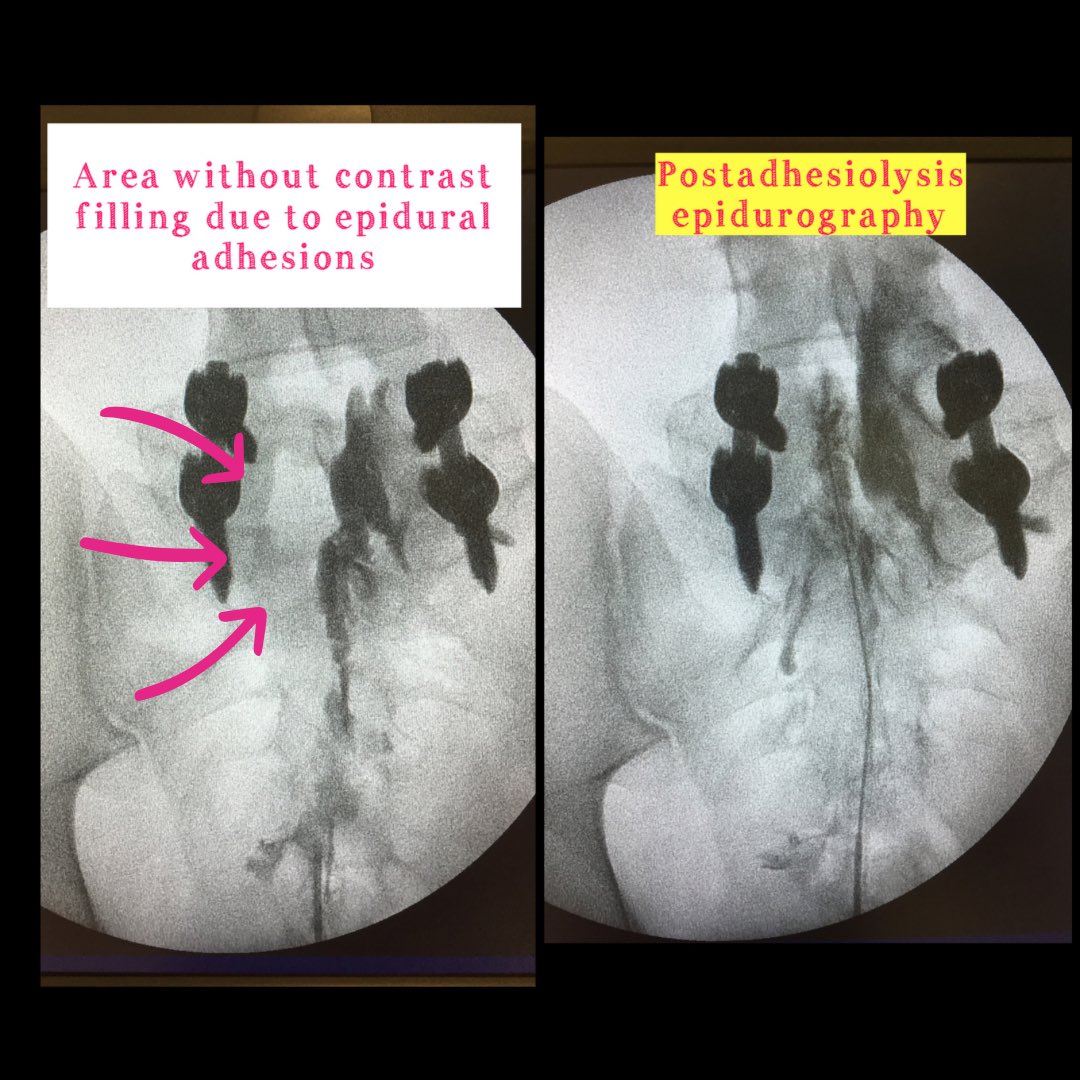

🔵Epidural neuroplasty🔵 ✅Normal epidurogram=Christmas tree pattern ❌Abnormal epidurogram=areas where the contrast does not fill epidural fibrosis 🚨Evidence for postlumbar surgery syndrome ClinicaEdolor Pain Center quirónsalud Bizkaia Vitoria #painrelief #pain

🔵Epidural neuroplasty🔵

✅Normal epidurogram=Christmas tree pattern

❌Abnormal epidurogram=areas where the contrast does not fill epidural fibrosis

🚨Evidence for postlumbar surgery syndrome

<a href="/ClinicaEdolor/">ClinicaEdolor</a> Pain Center <a href="/quironsalud/">quirónsalud</a> Bizkaia Vitoria